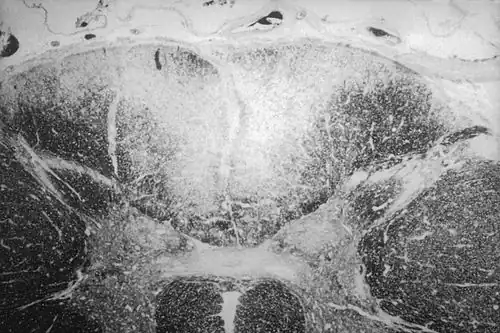

- zapalenie białe płuc (pneumonia alba)

- wytwórcze zapalenie śródmiąższowe w różnych narządach (nerki, serce, nadnercza, trzustka, śledziona).